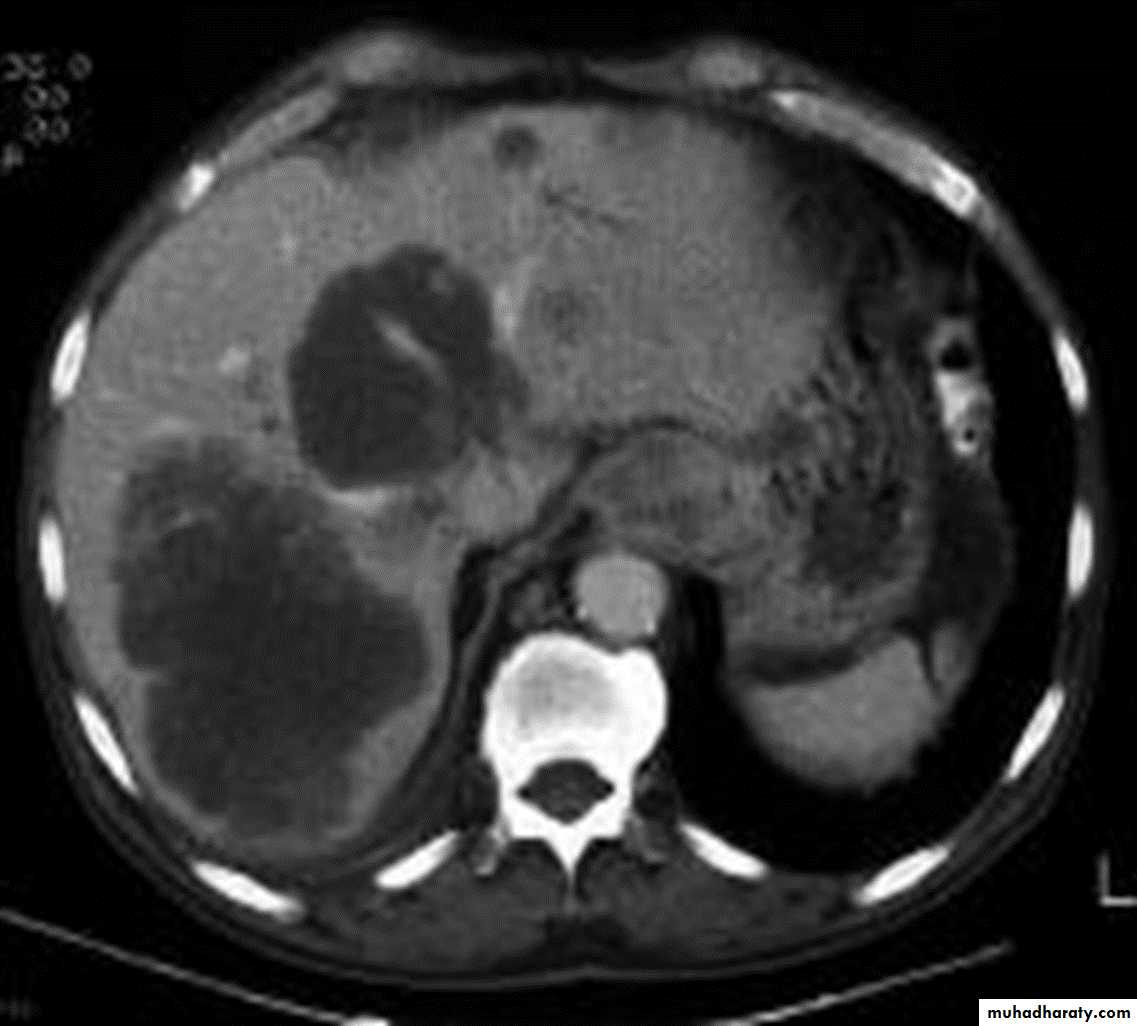

5. Assessment of the distant metastases

CT essential in the Dx & staging of the CA

4.Aortic invasion .

5.Osophageal CA is often metastatic at the time of presentation ( look for the LN & distal metastasis ) .